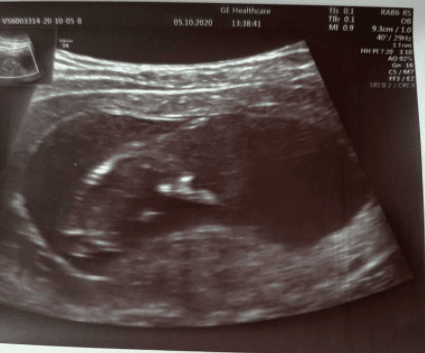

Pieknie! Gratulacje!!!Dzidzia❤ rośnie i sobie u Mamusi w brzuszku hula, narazie miejce maU mnie dzisiaj po wizycie na szczęście pozytywnieWszystko w porządku.. ciąża 11+3, dzieciaczek ruchliwy dosyć 46 mm

Wklejam Wam foteczkę

Zobacz załącznik 1184632